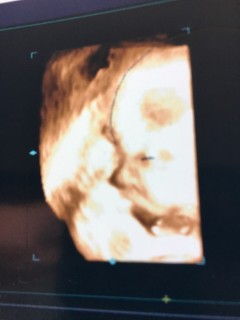

なかなか見れない週数に入りお顔を久々に見せてくれました!! 大きさは1860g程度、平均の大きさの女の子です。前回よりもお肉がついて赤ちゃんらしくなってきました。厚ぼったい唇は私に似ています。 目鼻立ちもしっかりしていると言われました!早く会いたくて仕方ないです。